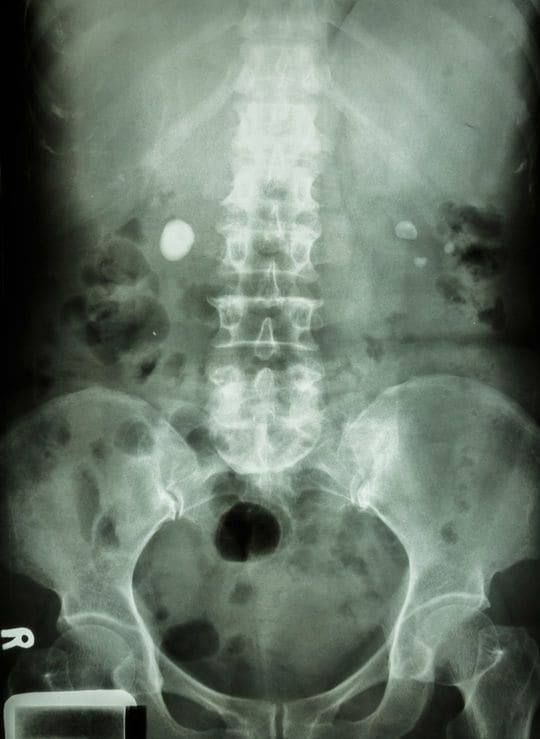

父親は50歳手前の頃、父親は下腹部の痛みを訴えながら数日間寝込んでいた。母親が何度「病院へ行こう」と言っても聞かず、激しい痛みに冷や汗を流しながら耐えていた。しかしついに、「救急車を呼んでくれ」と言う。

ただし、「近所に知られたらみっともないから、絶対にサイレンを鳴らさずに来るように言え」と念を押す。母親はその通りに伝え、救急車もその通りに来てくれた。

結果、父親は尿路結石だった。